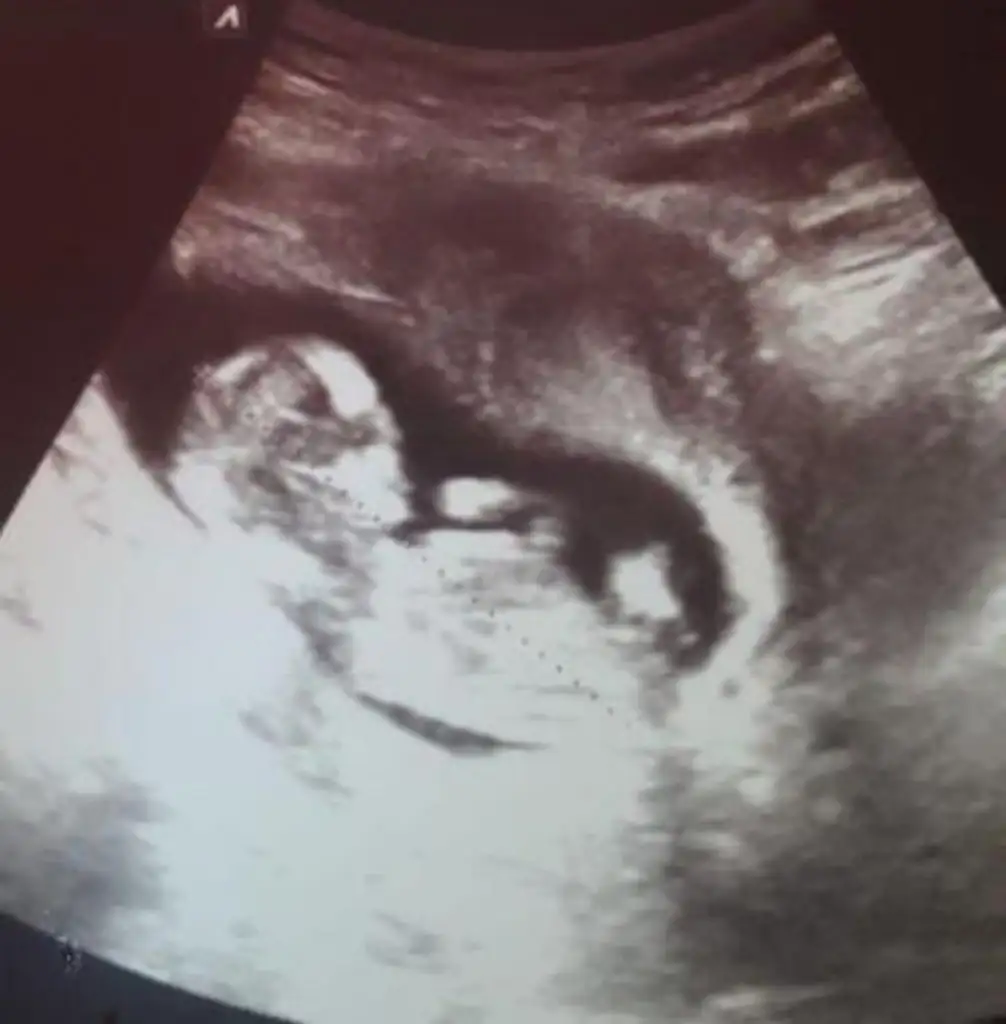

Kizz :)Bir başka ultrason istemiştiniz bunlar var elimde bacaklarini bağlamışti öylece duruyorduheyecanla yorumunuzu bekliyorumm Ikra meyra

Siz dışında herkes erkek dedi tecrubelimisiniz acaba bu konuda yorum yaptınız ona göre kafa karışıklığı yasayacamKizz :)

Eh iste ikra kadar degil tabiki o erkk dediyse erkektir sen yinede digerlerini dikkate al canim :)Siz dışında herkes erkek dedi tecrubelimisiniz acaba bu konuda yorum yaptınız ona göre kafa karışıklığı yasayacam

Kaç haftalık cnm sanki erkek emin olamadım başka usg de paylaş cnm dogum yaptınmı yapmışındır minnoş sen nasılsınızIkracim bu ne acaba yorumlarmisin